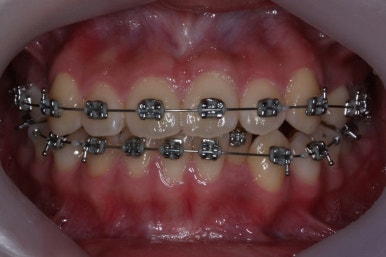

부산교정전문의 키다리아저씨치과에 처음 내원하셨을 때 당시의 입안 모습입니다.

윗니 뿐만 아니라 아랫니 부위에도 덧니가 관찰됩니다. 다른 앞니, 어금니 부위도 약간 삐뚤한 부분이 보입니다.